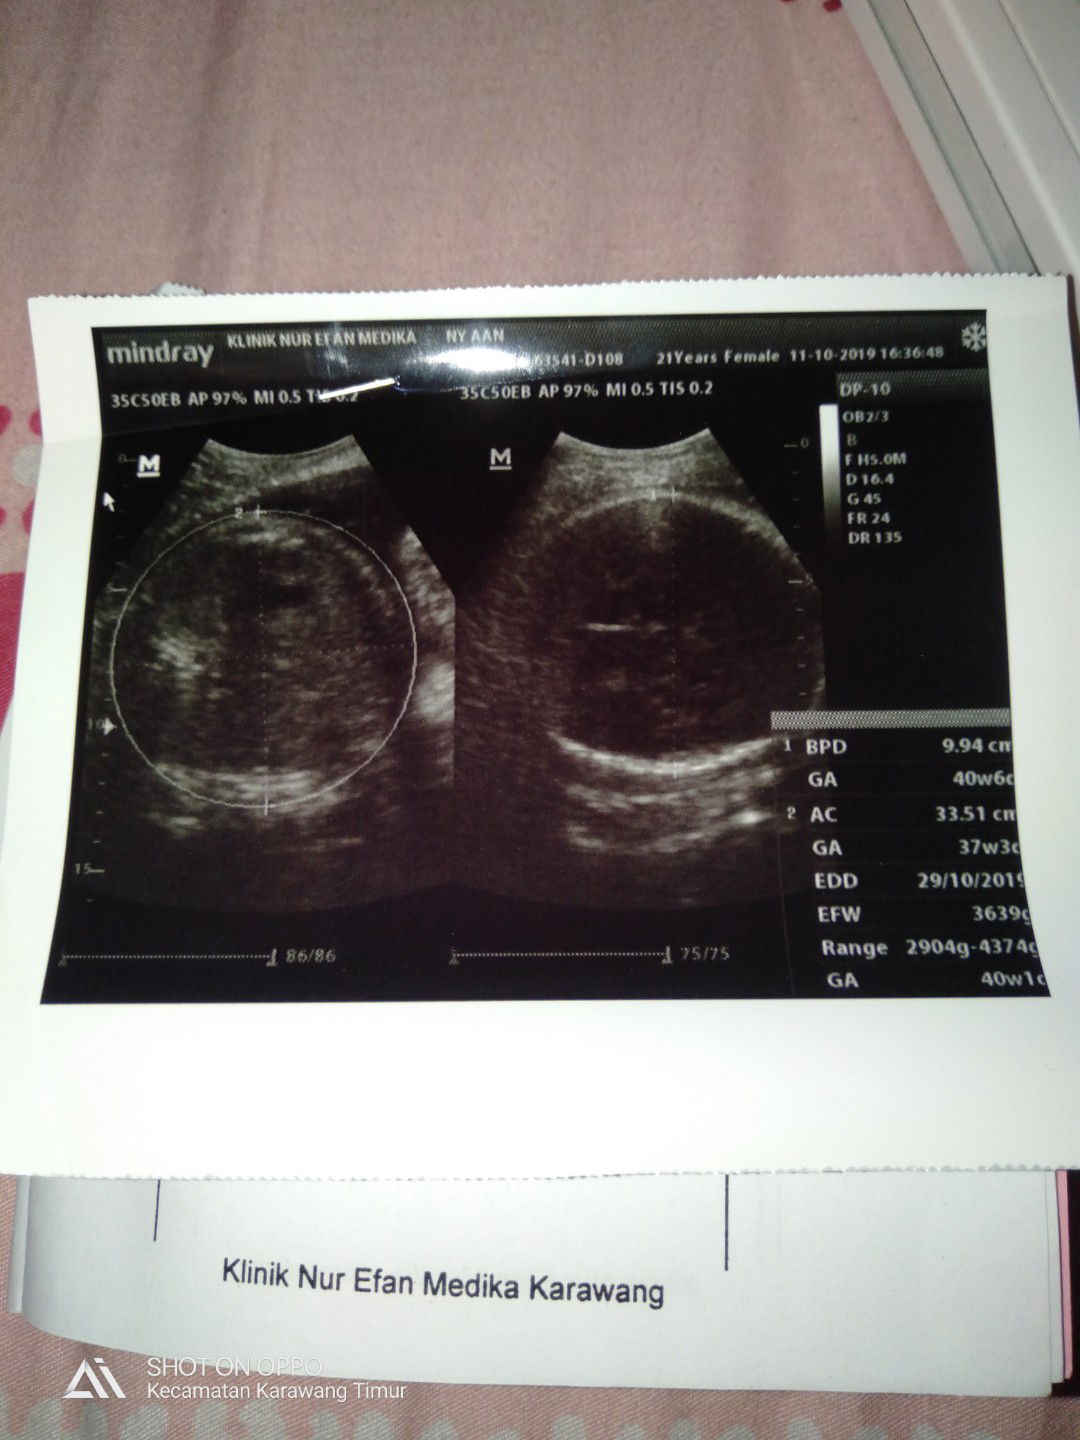

ibu hamil